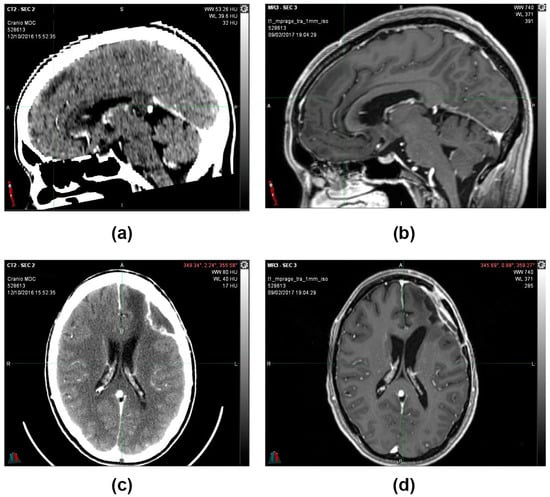

MRIs were done in subsequent periods (12 July 2021 and 11 October 2022), confirming that the morphological picture remained stable and that the patient was considered cured (Figure 5).

Figure 5.

(a) 21 August 2016, CT image with contrast medium before surgery. (b) 12 October 2016, CT image with contrast medium after partial removal of left frontal multicentric neoplasm. (c) 9 February 2017, MRI image, T1 sequence with contrast medium after the first cycle of oxygen-ozone therapy. (d) 12 July 2021, MRI image sequence in FLAIR. (e) 24 February 2022, MRI image sequence in FLAIR. (f) 11 October 2022, MRI image sequence in FLAIR. Following a total of 5 years after the partial resection surgery, the morphological picture remained stable, and the patient was considered cured.